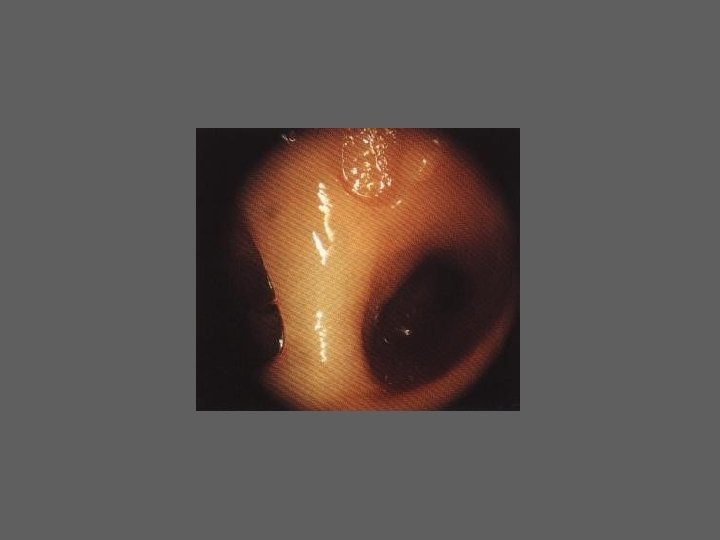

CELIOSCOPIA - TÉCNICA – Anestesia geral – Doente em posição ginecológica em inclinação Trendelenburg – Desinfecção e colocação de sonda endouterina – Inserção de agulha de Verres – Insuflação de 1 – 2 litros de CO 2 – Incisão de cerca de 1 cm no bordo inferior do umbigo – Introdução do Trocar – Introdução do celioscópico – 2ª via de acesso – Observação panorâmica e individualizada

HISTEROSCOPIA - INDICAÇÕES Todas a situações em que se julgue vantajosa uma visualização completa da cavidade uterina, em particular: – Metrorragias – Dismenorreia adquirida – Infertilidade – Abortamentos de repetição e parto pré-termo – HSG anormal – DIU “perdido” – GIFT e ZIFT – Tratamento cirúrgico da patologia intracavitária: ● pólipos, miomas, septos, sinéquias, recessões endometriais ● baixos custos, reduzida morbilidade